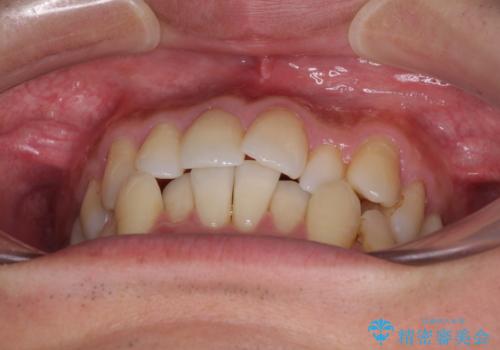

受け口傾向の咬み合わせ 前歯のデコボコをワイヤー矯正で素早く改善

- 前歯の見た目を気にして来院された患者様です。

ワイヤー矯正でもマウスピース矯正でも対応可能とお伝えし、非常に悩まれていましたが、2年後に転勤の可能性が高いとのことで、治療終了までの期間を想定しやすいワイヤー矯正にて治療を行うこととしました。

前歯のクロスバイトは、改善の途中で歯髄壊死を起こすリスクが高くなるため、マウスピース矯正よりもワイヤー矯正をお勧めしております。